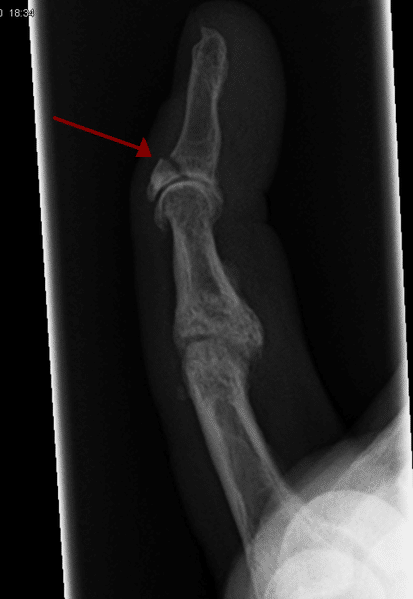

그날 저녁 내내 드리웠던 불안감은 다음날 정형외과 외래에서 실체로 나타났다. 왼쪽 네 번째 손가락 원위부 골절. 다행히 수술은 안 해도 될 것 같다고 말씀하셨다. 전치 6주의 골절 진단을 받고 앞으로의 불편함이 걱정되었지만 막상 진단을 받으니 마음이 좀 편해진다. 사람의 마음은 신기하다. 썩 좋은 결과가 아니라도 하더라도 불행의 결과를 알면 불안감은 어느 정도 사라진다. 예상할 수 없을 때, 정해진 것이 없을 때 이런저런 상상으로 스스로의 마음을 갉아먹는 것이 사람의 마음인 것이다.